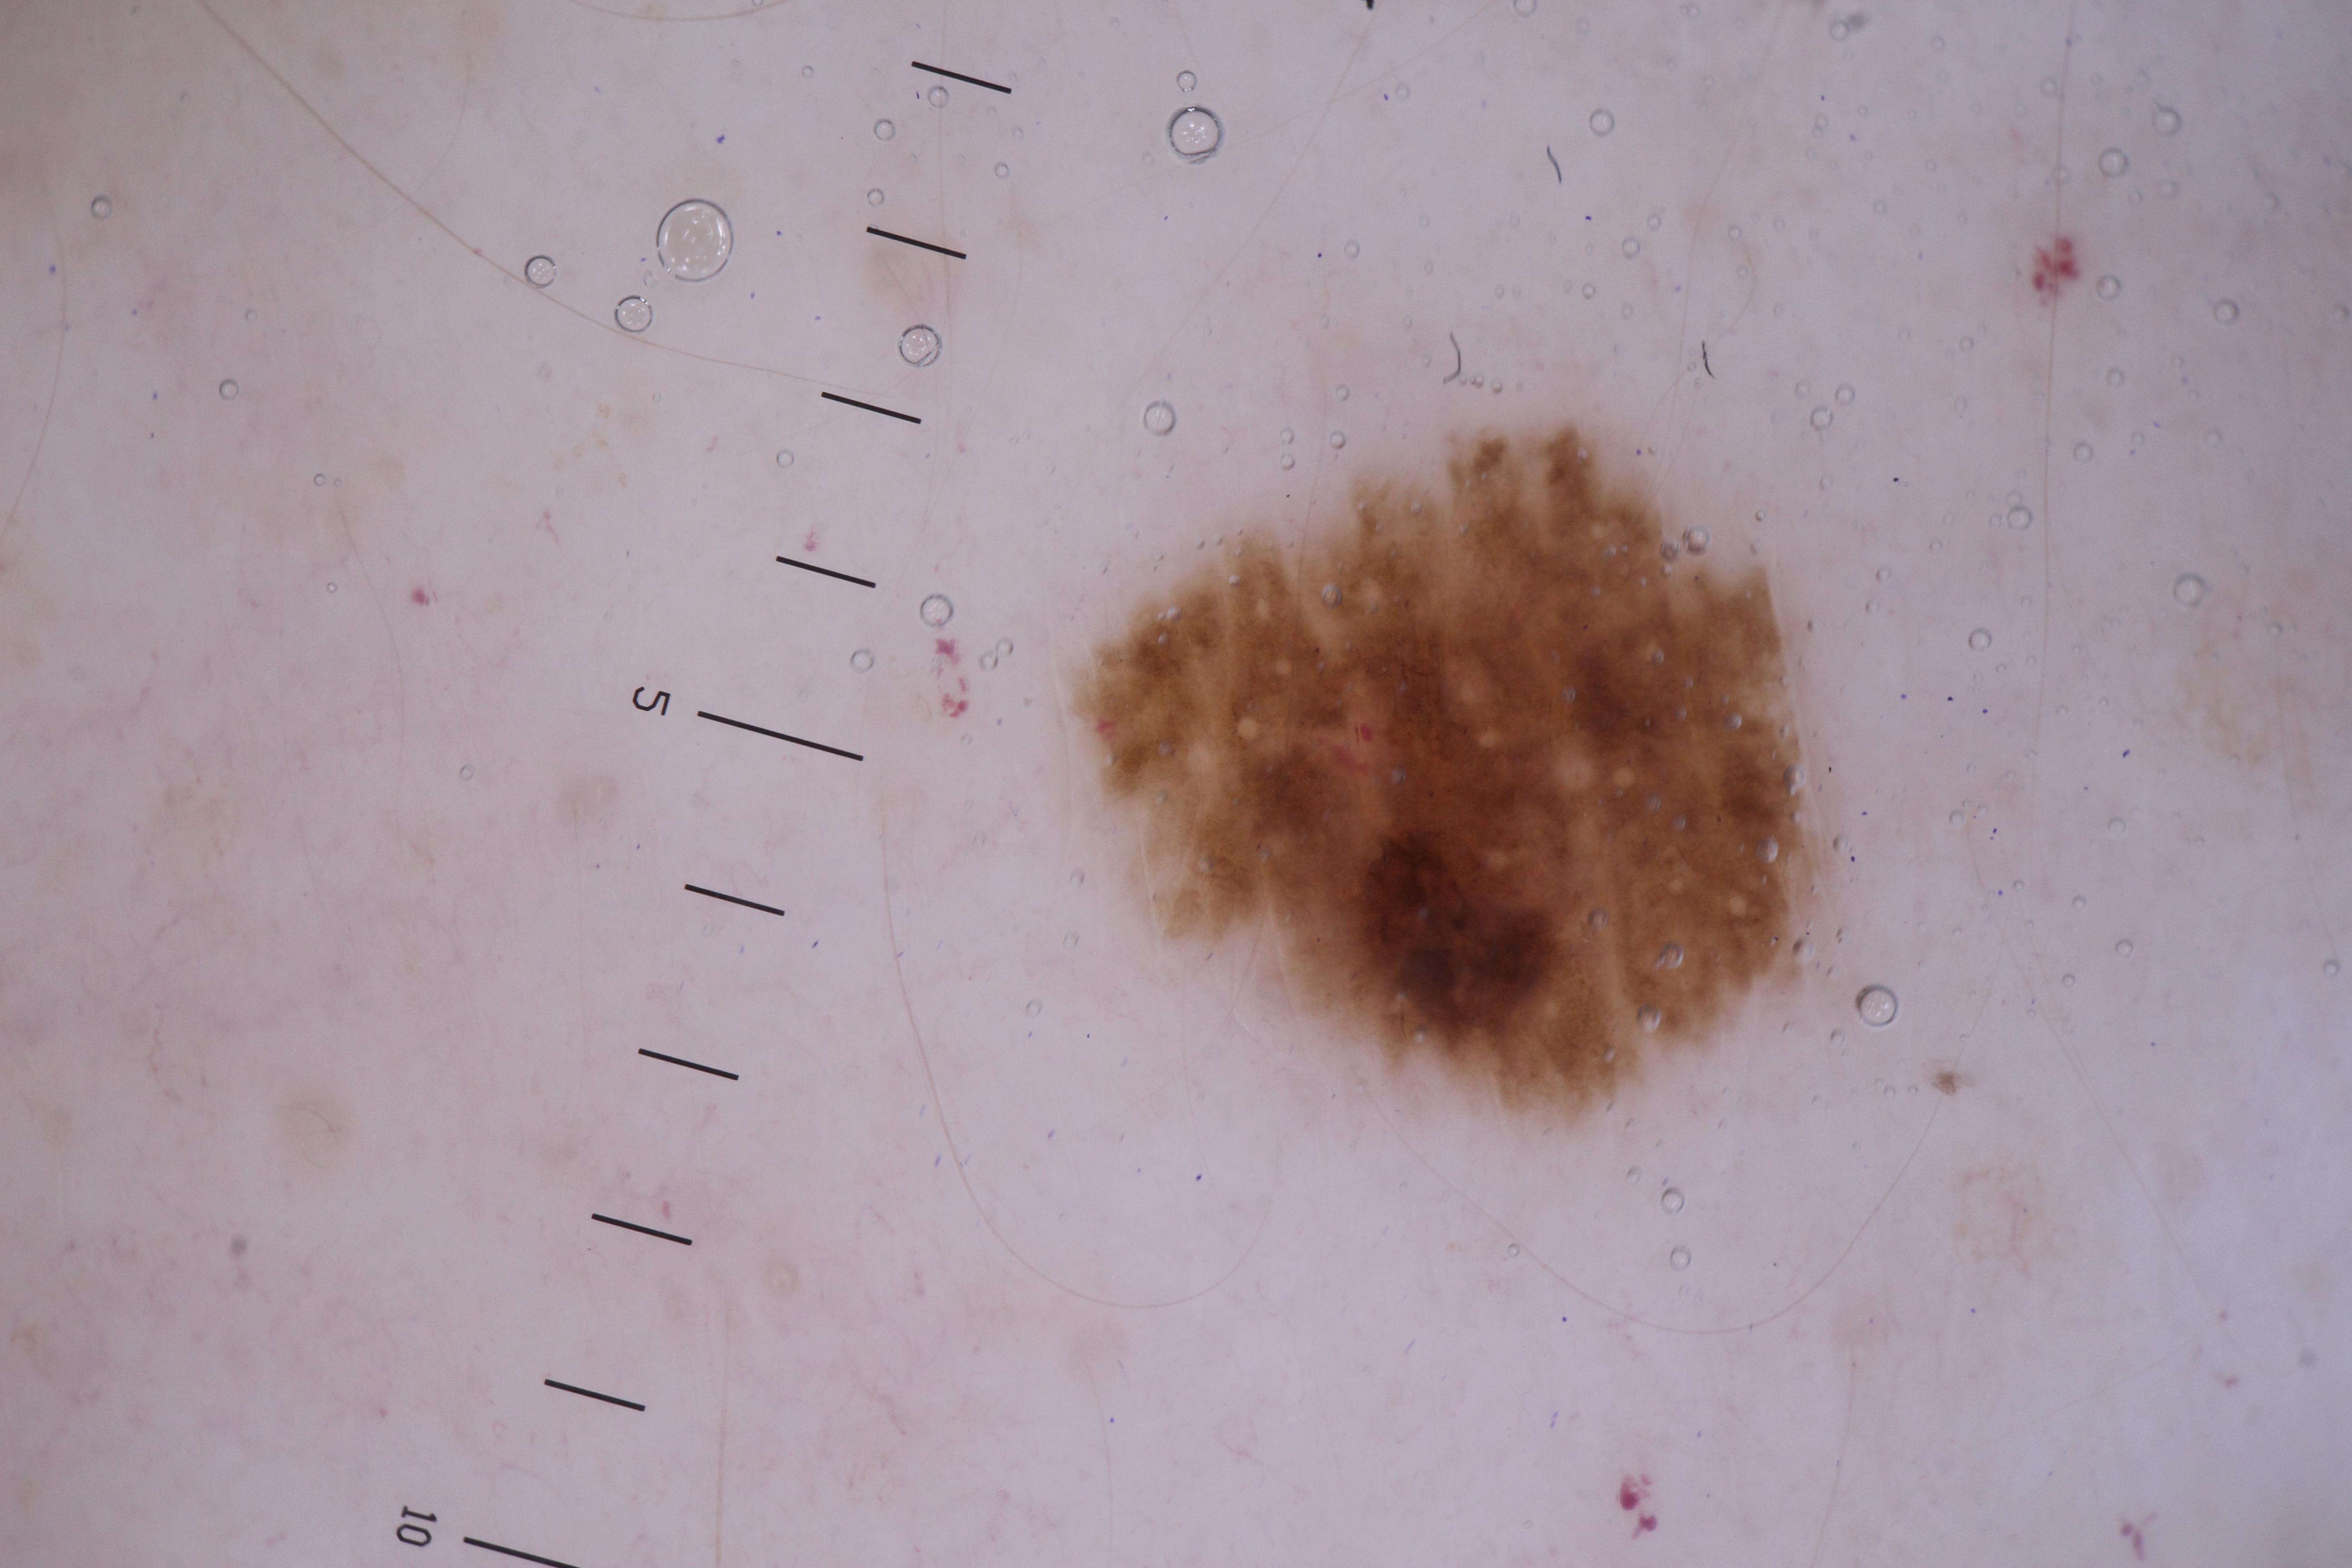

{

"acquisition_day": 170,

"age_approx": 45,

"anatom_site_general": "upper extremity",

"concomitant_biopsy": false,

"diagnosis_1": "Malignant",

"diagnosis_2": "Malignant melanocytic proliferations (Melanoma)",

"diagnosis_3": "Melanoma, NOS",

"diagnosis_confirm_type": "histopathology",

"fitzpatrick_skin_type": "III",

"image_type": "dermoscopic",

"lesion_id": "IL_7889283",

"melanocytic": true,

"patient_id": "IP_5394240",

"sex": "male"

}